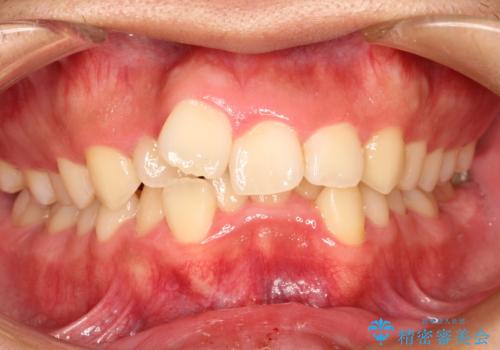

インビザラインチェンジで成功 インビザラインで八重歯の抜歯矯正